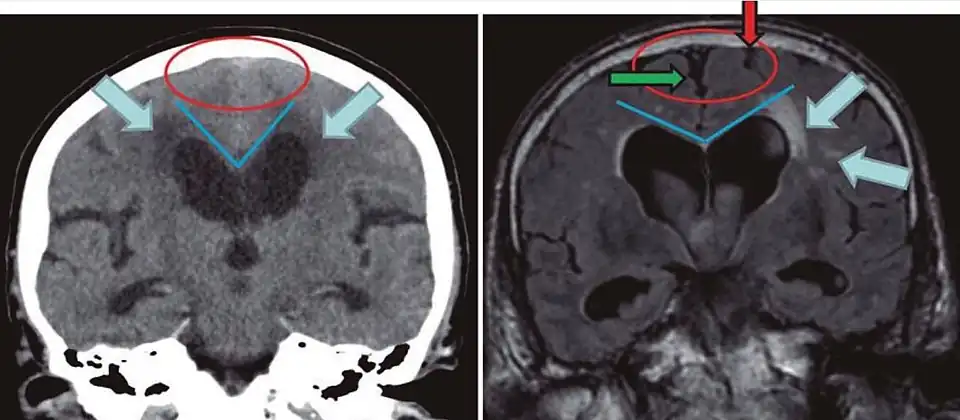

Difference from hydrocephalus

Cerebral atrophy can be hard to distinguish from hydrocephalus because both cerebral atrophy and hydrocephalus involve an increase in cerebrospinal fluid (CSF) volume. In cerebral atrophy, this increase in CSF volume comes as a result of the decrease in cortical volume. In hydrocephalus, the increase in volume happens due to the CSF itself.[20]

| Normal pressure hydrocephalus | Brain atrophy | |

|---|---|---|

| Preferable projection | Coronal plane at the level of the posterior commissure of the brain. | |

| Modality in this example | CT | MRI |

| CSF spaces over the convexity near the vertex (red ellipse |

Narrowed convexity ("tight convexity") as well as medial cisterns | Widened vertex (red arrow) and medial cisterns (green arrow) |

| Callosal angle (blue V) | Acute angle | Obtuse angle |

| Most likely cause of leucoaraiosis (periventricular signal alterations, blue arrows |

Transependymal cerebrospinal fluid diapedesis | Vascular encephalopathy, in this case suggested by unilateral occurrence |